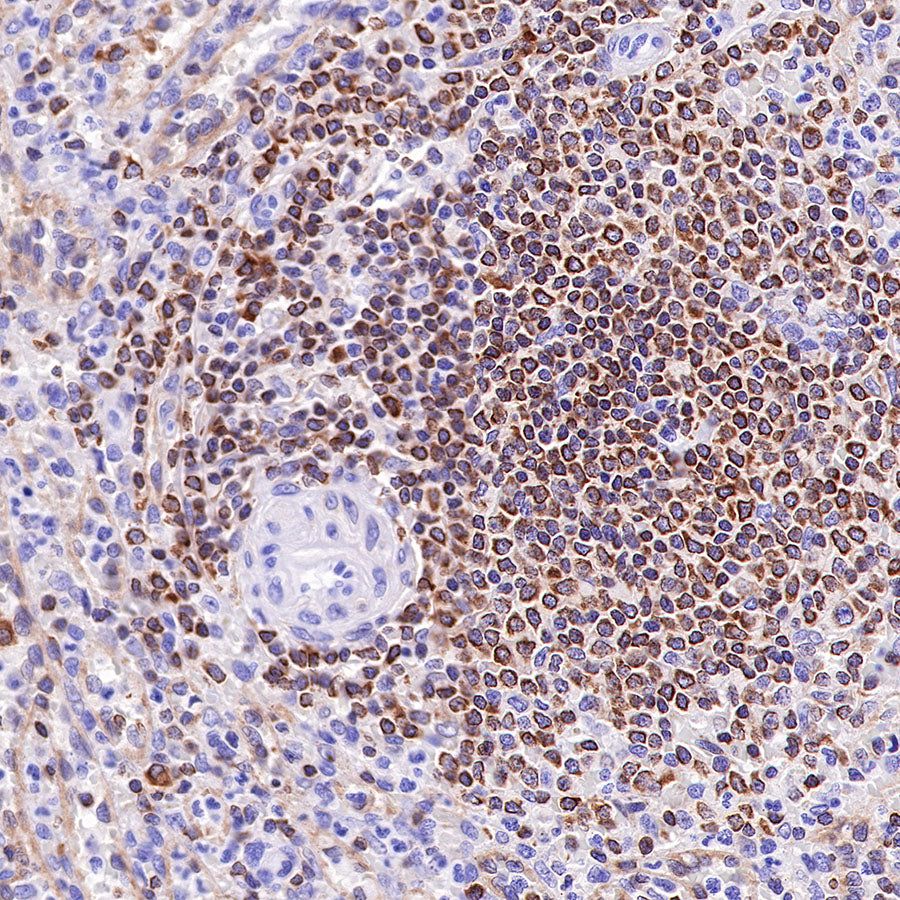

Picture

Picture

Immunohistochemistry